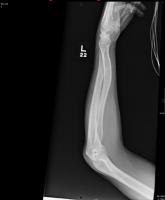

After accidentally being run over by a vehicle, a 54-year-old man presents to the emergency department for evaluation of pain in his elbow and left ar...